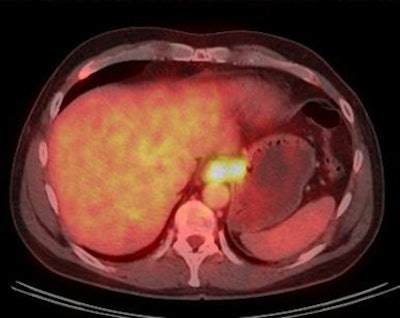

Images show carcinoma at the esophagogastric junction before therapy (pre therapy) and after two cycles of chemotherapy (post therapy). The image after two cycles of chemotherapy demonstrates complete metabolic response. Image courtesy of Dr. Gerald Antoch.Understanding the technical basics of hybrid imaging is vital for doctors keen to avoid the trap of misinterpreting artefacts as pathological findings. Specifically, attendees at today's basic session will discover how morphological and functional imaging interact and how this interaction may lead to false positives or lower quality pictures, according to moderator Dr. Gerald Antoch, chair of radiology at Düsseldorf University Hospital in Germany.